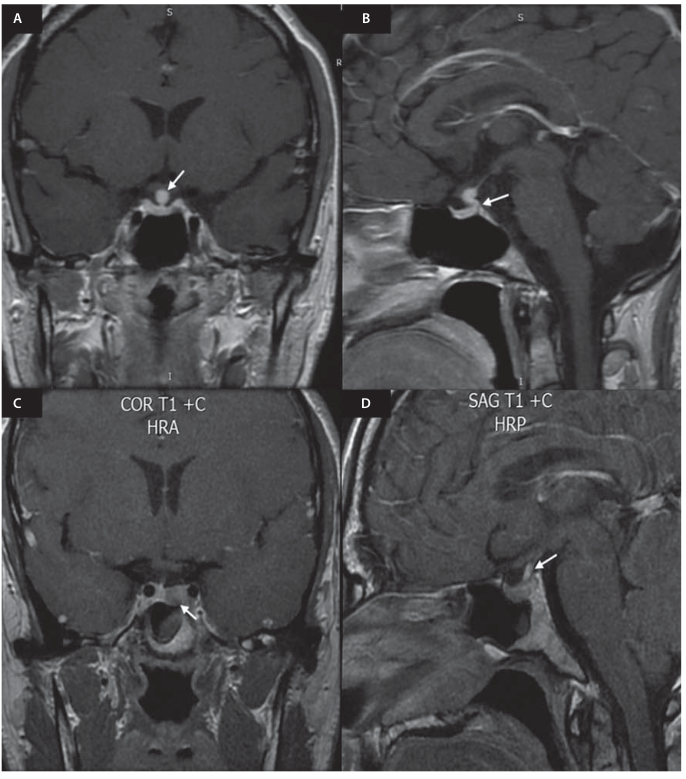

Figura 1: IRM con gadolinio proyección T1. A. Paciente 1: imagen coronal, hiperintensidad homogénea de la hipófisis, con aumento del volumen y extensión supraselar (flecha blanca). B. Paciente 1: imagen sagital, ausencia de hiperintensidad en la hipófisis posterior (flecha blanca). C. Paciente 2: imagen coronal, aumento del volumen hipofisario izquierdo con adenoma de 9 x 6 mm (flecha blanca) y desviación del tallo hipofisario a la derecha. D. Paciente 2: imagen sagital, hiperintensidad del tallo hipofisario (flecha blanca) con apariencia pseudotriangular (infundibulitis) y ausencia de hiperintensidad de la hipófisis posterior.

Dada la persistencia de la sintomatología, se realizó una prueba de restricción hídrica (Tabla 1) compatible con diabetes insípida de origen central. Se solicitó una imagen de resonancia magnética (IRM) con gadolinio sugestiva de hipofisitis (Figura 1 A y B). Se inició el manejo con desmopresina 60 μg sublingual cada 12 horas y presentó mejoría de los síntomas. Se descartaron causas infecciosas (serología VDRL no reactiva, virus de la inmunodeficiencia humana [VIH] negativo, sin clínica de tuberculosis o bacteriemia) y autoinmunes (anticuerpos antinucleares [ANA] por inmunofluorescencia indirecta [IFI] < 1/40 diluciones, sin clínica de enfermedad autoinmune asociada), o hipofisitis asociada a inmunoglobulina G 4 (IgG4) (inmunoglobulina G [IgG]: 820 mg/dL, valor de referencia [VR]: 650-1600 mg/dL; IgG4: 12 mg/dL, VR: 4-86 mg/dL; inmunoglobulina M [IgM]: 110 mg/dL, VR: 54-300 mg/dL; inmunoglobulina A [IgA]: 120 mg/dL, VR: 40-350 mg/dL). Los estudios complementarios de hipófisis anterior, a excepción de la prolactina, estuvieron dentro de los límites normales (factor de crecimiento insulínico tipo 1 [IGF-1] 112 ng/mL, VR: 88 -537 ng/mL; prolactina 32,11 ng/mL, VR: 5,18-26,53 ng/mL; cortisol sérico: 18,50 μg/dL, VR: 3,7-19,4 μg/dL; y tirotropina [TSH]: 0,88 μUI/mL, VR: 0,46-4,68 μUI/mL; tiroxina [T4] libre normal). Debido a la resolución espontánea de la galactorrea con la reaparición de ciclos menstruales y el seguimiento de la prolactina con normalización en los niveles, no requirió manejo con agonistas de dopamina.

Los resultados evidenciaron una osmolalidad urinaria menor de 300 mOsm/kg (resultado en 222 mOsm/kg) y hormona antidiurética ¡ 2 pg/mL (resultado en 1 pg/mL), con gasto urinario de 4,3 mL/kg/h (volumen urinario: 8300 mL/24 horas), por lo cual se confirmó la diabetes insípida. Se descartaron causas secundarias de poliuria. En la IRM de silla turca con gadolinio (Figura 1) se observó una imagen compatible con microadenoma (Figura 1C), con aumento del tamaño en hemihipófisis izquierda y desviación del tallo hipofisario a la derecha, con una imagen pseudotriangular del infundíbulo (Figura 1D) y ausencia de hiperintensidad en T1 de la hipófisis posterior. Se consideró un cuadro de hipofisitis con diabetes insípida central. Teniendo en cuenta el antecedente de patología rinosinusal, se inició la terapia con desmopresina orodispersable, con titulación de dosis hasta 120 µg cada 12 horas, y se presentó mejoría del gasto urinario y la polidipsia. Los estudios complementarios hipofisarios descartaron funcionalidad del microadenoma (IGF-1: 160 ng/mL, VR: 71,2-234; prolactina: 11,4 ng/mL, VR: 4,04-15,2; cortisol a. m.: 10,2 μg/dL, VR: 4,82-19,5; TSH: 1,77 μUI/mL, VR: 0,27-4,2; T4 libre: 1,39 ng/dL, VR: 0,93-1,7). El paciente no tiene síntomas o alteraciones en los paraclínicos sugestivos de enfermedad autoinmune, granulomatosa o infecciosa que sugieran causas secundarias de hipofisitis.

Los hallazgos característicos en la IRM cerebral son la hiperintensidad homogénea de la hipófisis anterior, con aumento del volumen hipofisario de predominio supraselar e hiperintensidad de la duramadre adyacente (signo del tallo dural). En caso de infundibulitis, se puede observar hiperintensidad con apariencia pseudotriangular del infundíbulo y pérdida de la hiperintensidad de la hipófisis posterior en T1 cuando se asocia con diabetes insípida [3, 16, 17], tal como se describe en los dos presentes casos. Estos signos son más frecuentes en la hipofisitis linfocítica clásica. El compromiso aislado del tallo hipofisario es más común en la hipofisitis linfocítica, histiocitosis de Langerhans, tumores de células germinales o metástasis [18]. Los hallazgos de silla turca vacía pueden encontrarse como resultado del proceso inflamatorio crónico.